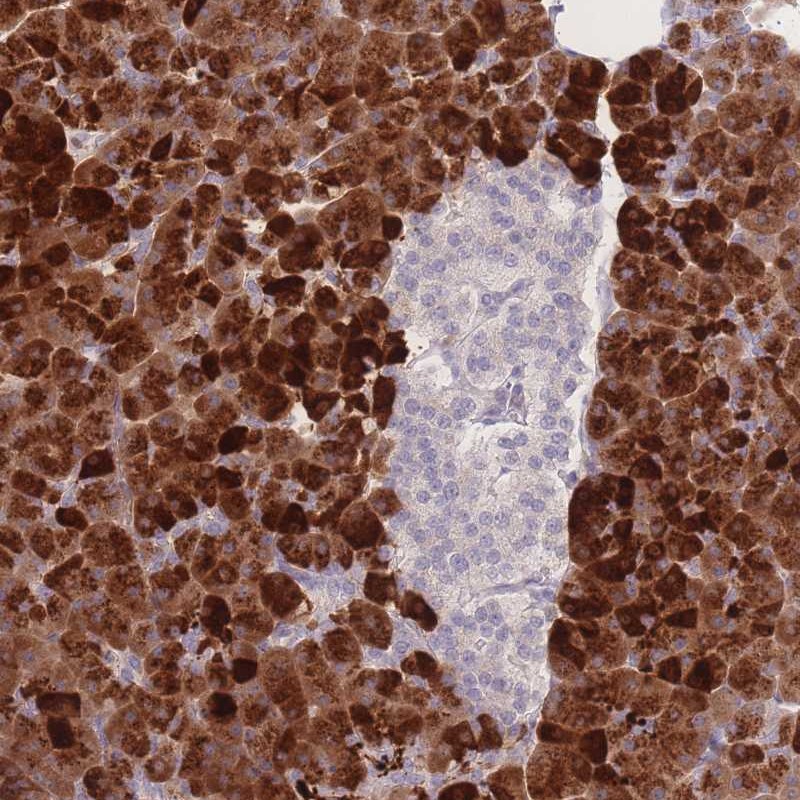

Immunohistochemical staining of human pancreas shows strong cytoplasmic positivity in exocrine glandular cells.